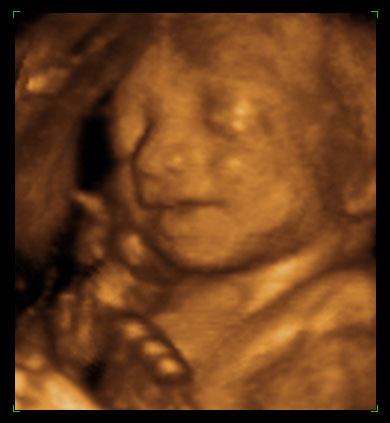

ултразвучни приказ бебе 24. недеље трудноће (2)